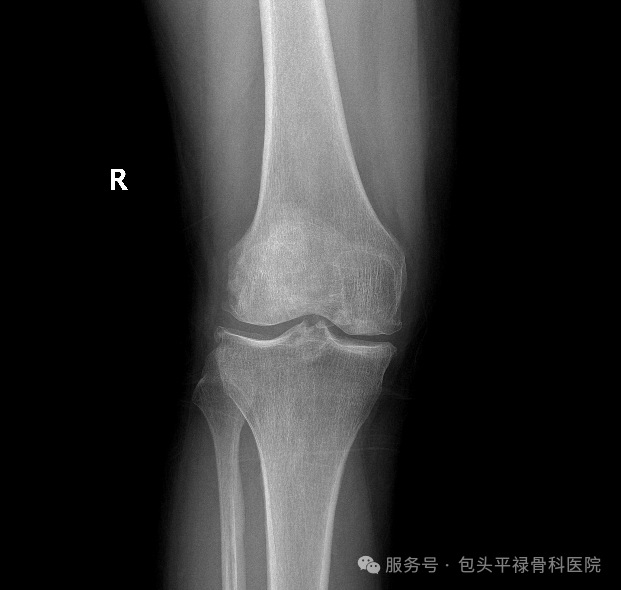

右膝关节游离体,图源:包头平禄骨科医院

膝关节游离体,就是膝关节里多出来的一些“碎骨头”或“碎软骨”,甚至是增生的小骨头等,它们形态各异,大小不同,小的像米粒,大的能有蚕豆大,数量可能1个,也可能好几个,像老鼠一样在关节里到处跑,所以又叫关节鼠。